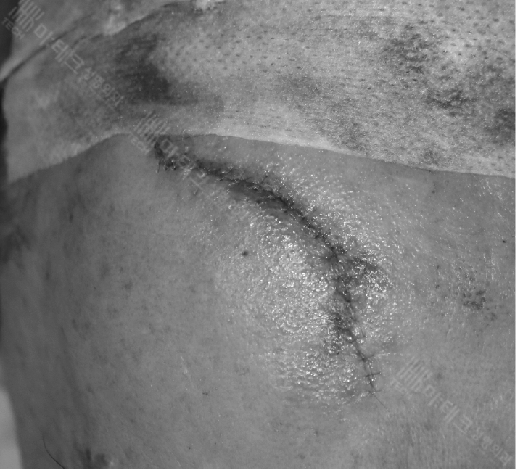

이마 부위에 약 8cm가량의 긴 상처가 생긴 분입니다.

수술 직후 240326

미세봉합수술을 마치고 바로 촬영한 사진입니다.

이러한 얼굴 상처봉합은 근육층부터 피하지방층,

피부층까지 3중으로 꼼꼼하게 봉합을 하여야 흉터가 덜 남게 됩니다.

피부층만 봉합을 하게 되면 겉으로 보기에는 봉합이 잘 된 것처럼 보일 수 있으나 추후 봉합부위가 움푹 패일 수 있습니다.